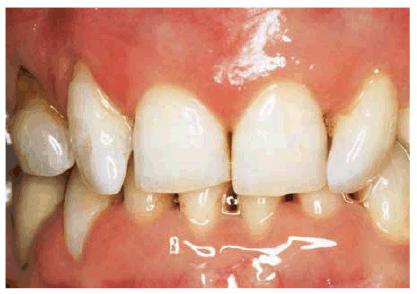

Gingival Architecture

An often overlooked component of an esthetic smile is the gingival

architecture. When there is crowding in the anterior region, certain teeth will

be forced facially or lingually. In a Class II, Division 2 occlusion, for

example, the maxillary lateral incisors may be positioned labially, and the

gingival tissue will be forced more apically. This creates a discontinuity in

the overall smile of the patient. Treatment considerations in this situation

may require slight modification to the gingival architecture around the central

incisors to create a more harmonious smile. If the patient's lip line hides the

gingival discrepancy, then surgical intervention may not be necessary (Figures 24-2A 24-2B 24-2C, and 24-2D

Figure 24-2A: This patient was dissatisfied with her crowded anterior teeth. Note how the gingival height differs between the central and lateral incisors.

Figure 24-2B: The dissimilar gingival heights did not bother the patient because her natural smile line concealed these irregularities.

Figure

24-2C: After a slight reproportioning of the six anterior teeth, direct

composite resin was placed and contoured (6-mm ET [Brasseler,

Figure 24-2D: The final result shows improved proportion in tooth size and form.